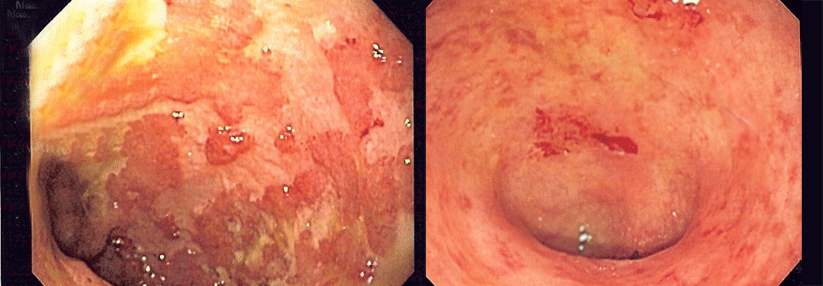

Zu viel Auswahl fördert nicht gerade die Entschlossenheit. Das gilt auch für die Therapie chronisch entzündlicher Darmerkrankungen mit Biologika. Professor Dr. Andreas Stallmach stellt sein persönliches Schema vor.

Spricht ein Patient mit einer chronisch entzündlichen Darmerkrankung (CED) nicht auf Steroide oder Azathioprin an, steht inzwischen eine Reihe von Biologika zur Verfügung. Doch welches nimmt man zuerst? Bei der Beantwortung dieser Frage helfen Head-to-head-Vergleiche – doch die gibt es für die CED-Biologika nicht, bedauerte Professor Dr. Andreas Stallmach von der Gastroenterologie, Hepatologie und Infektiologie am Universitätsklinikum Jena.